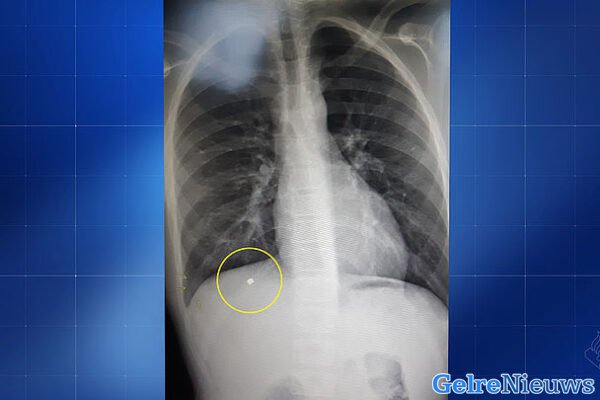

Het projectiel – waarschijnlijk een klein kogeltje – heeft een rib van de jongen gebroken. Daarna is het via zijn rechterlong in zijn lever beland. De rib heeft ervoor gezorgd dat het projectiel is afgeremd en er daardoor geen andere vitale organen zijn geraakt. Het verwijderen van het projectiel bleek erg riskant, waardoor artsen hebben besloten het kogeltje in de lever te laten zitten, meldt opsporing verzocht dinsdagavond.